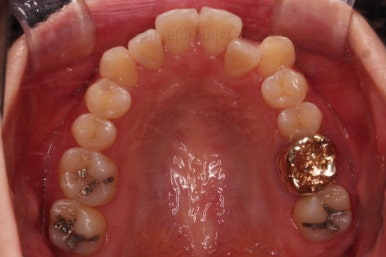

초진 시, 입안의 모습입니다.

좌측 송곳니가 덧니처럼 튀어나가 있고, 송곳니 옆의 작은 억므니가 안으로 쏙 들어가서 덧니 느낌이 더 강조되어 보이네요.

이번에 선택하신 장치는 자가결찰 세라믹 중에 엠파워 클리어라는 장치인데요.

흔히들 아시는 클리피씨도 같은 분류의 장치입니다.

철사가 들어가니 삐뚤한 치열이 더 강조되어 보이네요.